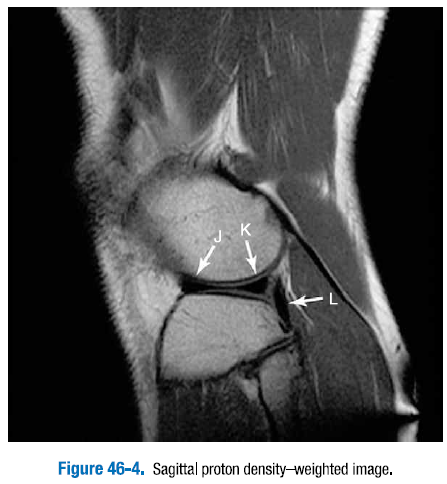

3. 그림 46-1 ~ 그림 46.4에 있는 무릎의 표지된 정상 구조물을 확인하라.

F. 전방십자인대   G. 후방십자인대   H. 슬개골건   I. 대퇴사두근건

J. 외측반월판 전방각   K. 외측반월판 후방각   L. 슬와근건